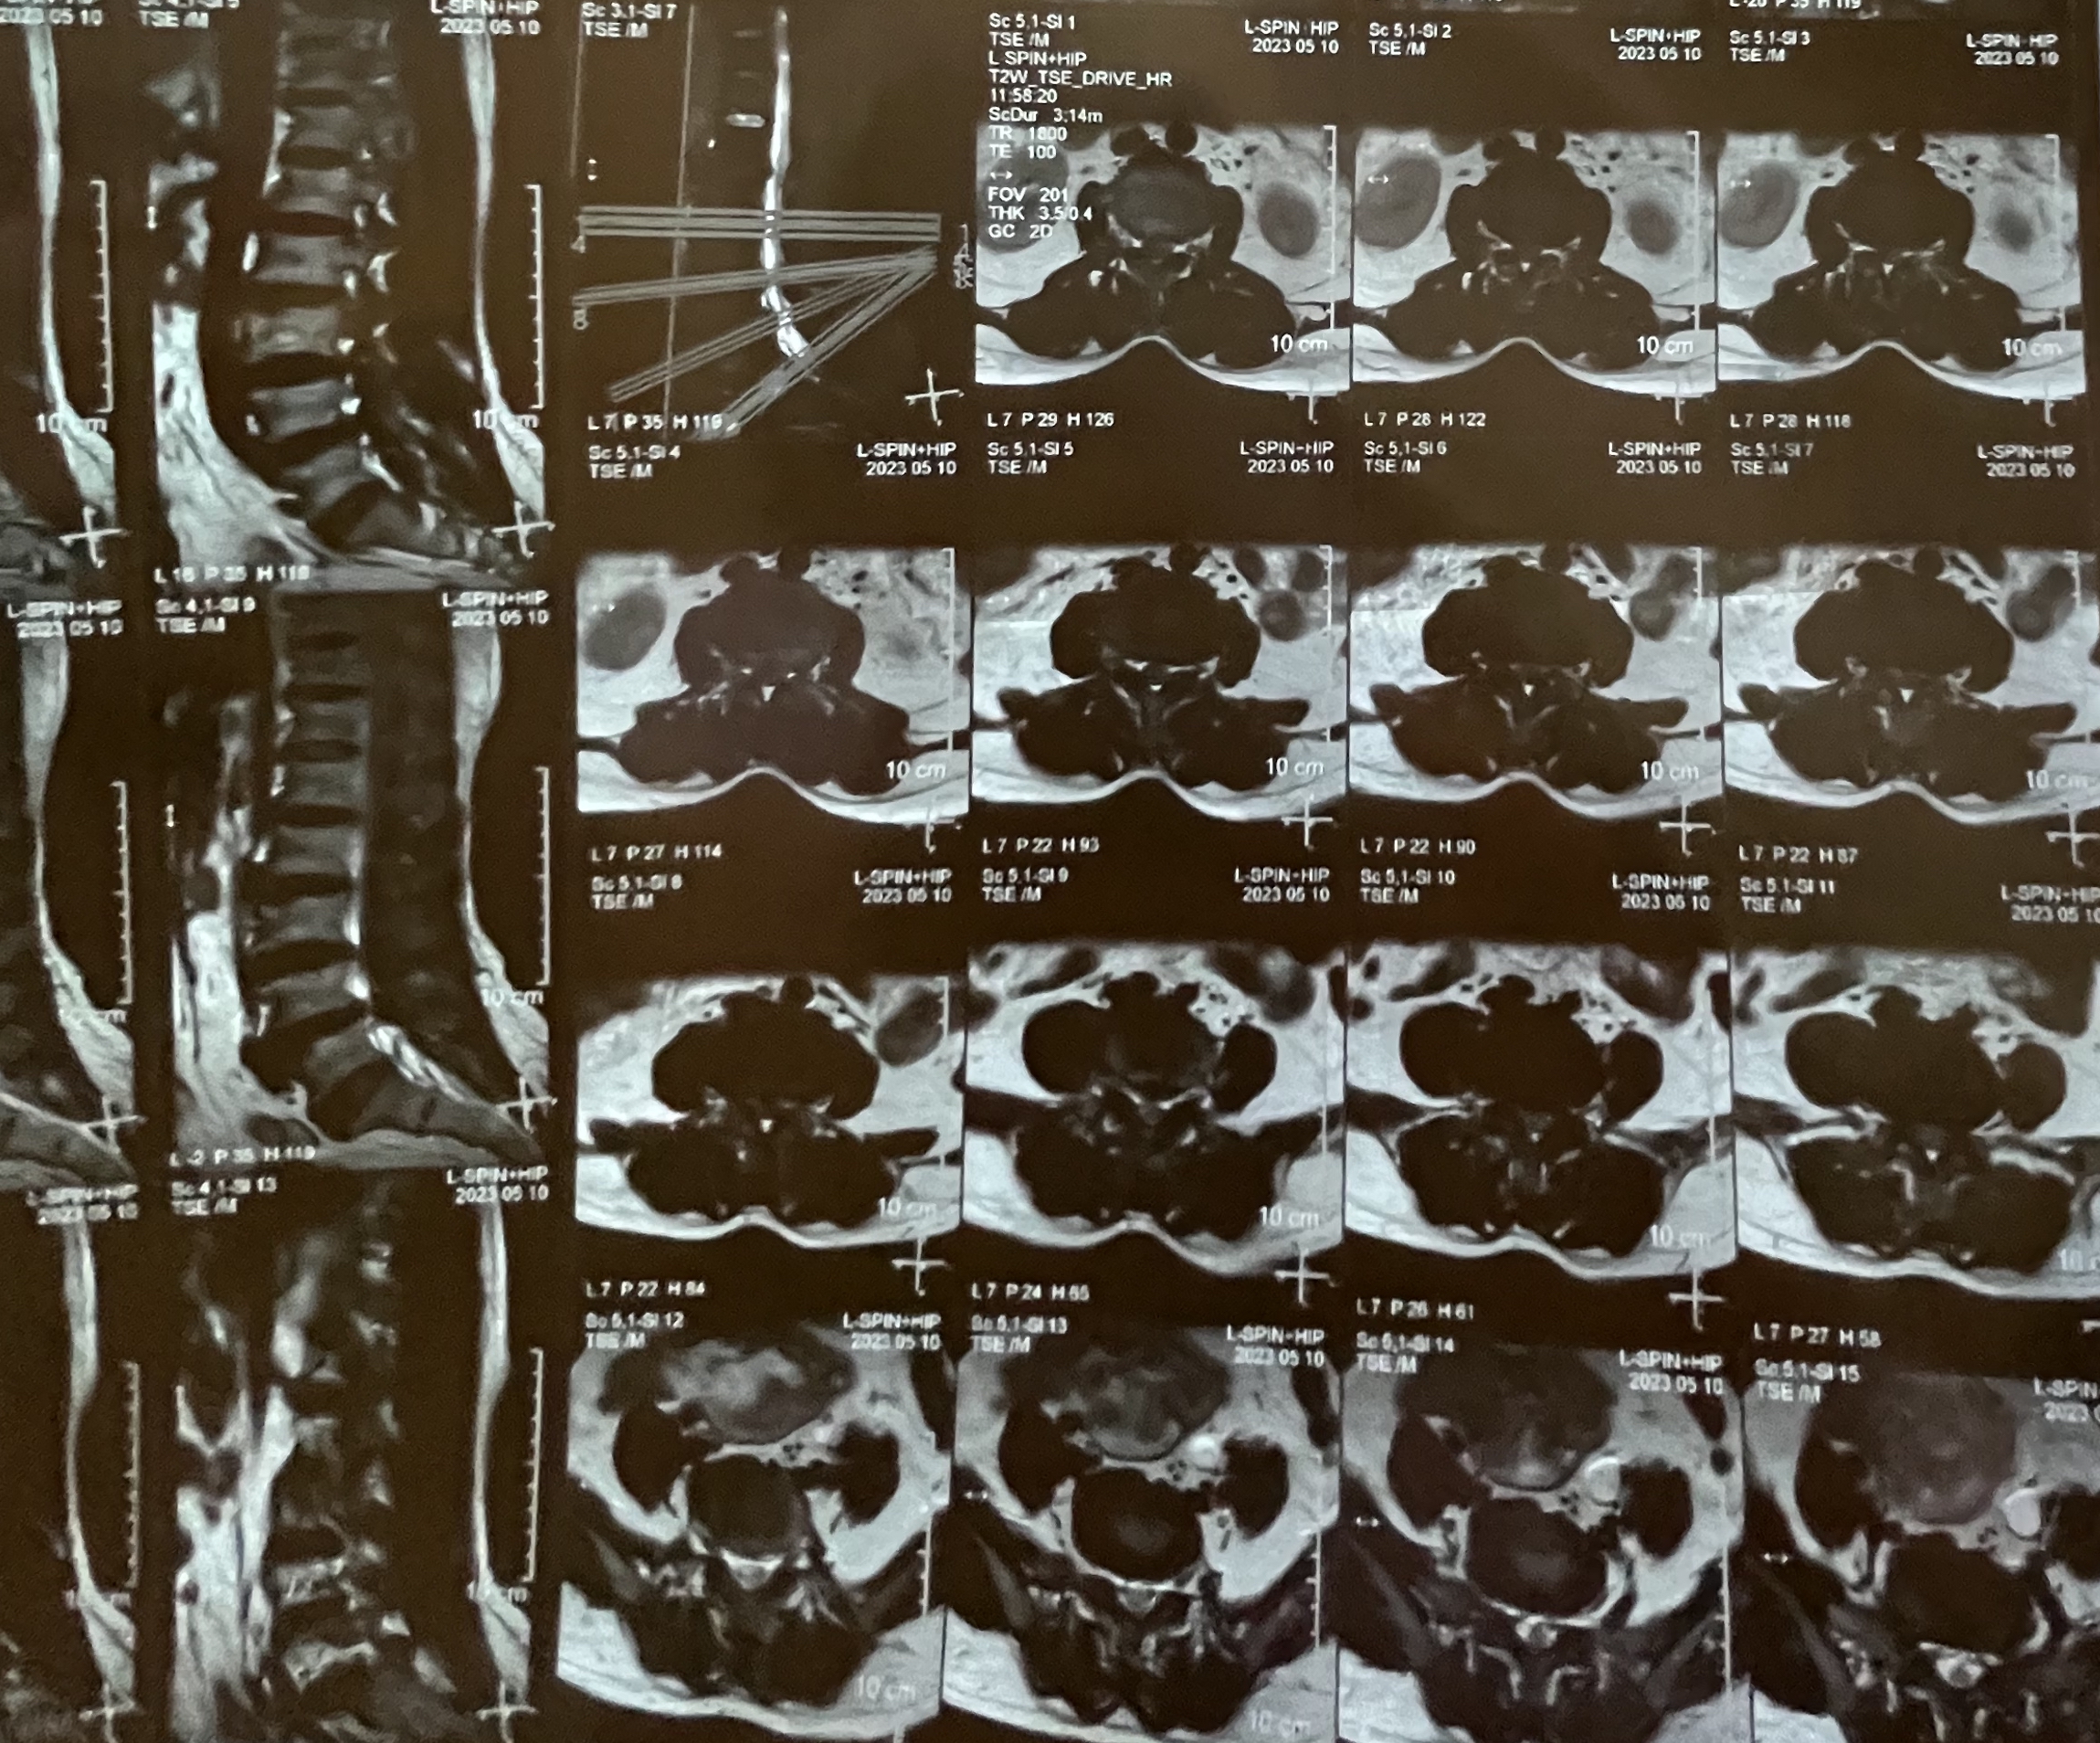

【结果】福永人民医院MR报:腰椎退行性变;L3/4、L4/5椎间盘膨出;左侧股骨头改变,考虑股骨头缺血性坏死。

腰椎曲度增大,腰部肌肉紧张、压痛(-),腰部叩击痛(-)、无放射痛,直腿抬高试验(-),排除低位“腰椎间盘突出症”。MR见 L3/4、L4/5椎间盘膨出,无神经根受压,排除“腰椎间盘突出症”。

左侧环跳穴压痛(+),腹股沟中点压痛(+),“4”字试验(+),痛点位于腹股沟中点,髋关节屈伸受限。骨盆平片阅片见左侧髋关节内侧间隙变宽、上方间隙变窄,股骨头外形欠圆滑,内见椭圆形低密度区。故高度怀疑“股骨头坏死”。 MR报左侧股骨头改变,考虑股骨头缺血性坏死,确认“股骨头缺血性坏死”临床诊断。